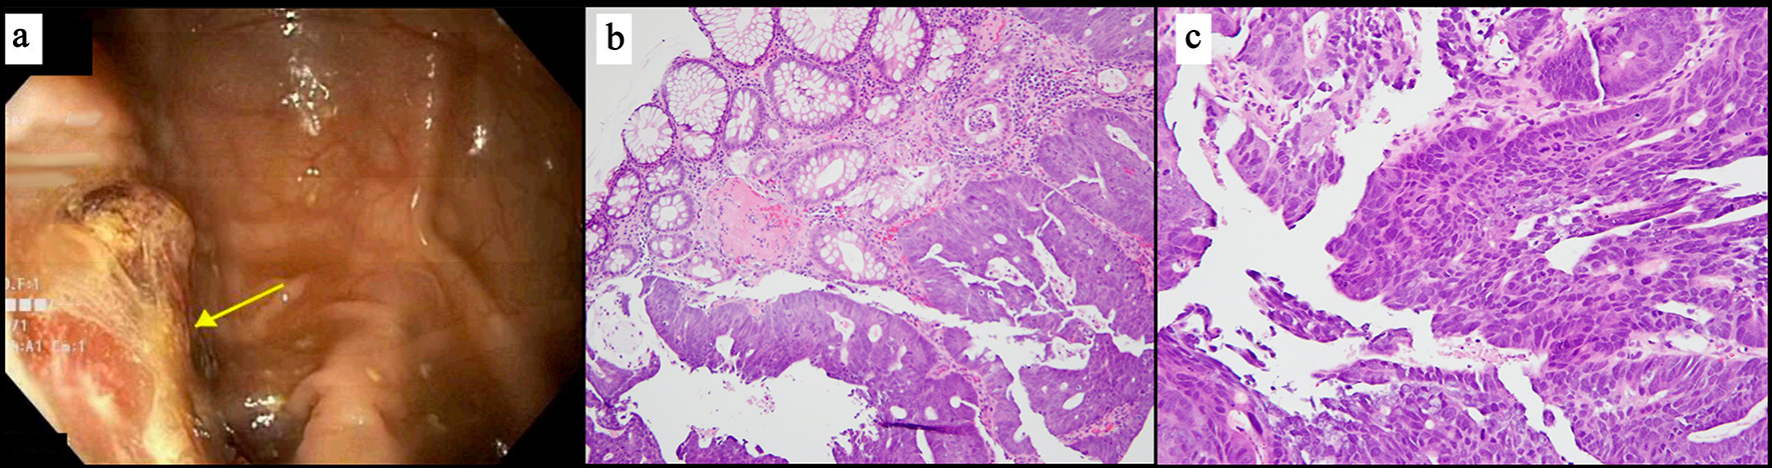

A 72 years old male with past medical history of chronic healed lower extremity ulcers due to lymphedema was brought to the hospital for evaluation of fever and altered mental status. On admission, vital signs showed temperature 39.1 °C, heart rate 92 beats/min, and respiratory rate 22 breaths/min. Physical examination was remarkable for pallor, systolic murmur along the aortic area. Lungs were clear to auscultation. Abdomen was soft, non-tender, and no organomegally was detected. Examination of the extremities showed multiple healed wounds along both the lower extremities without evidence of infection. His right ankle was swollen and mildly tender to palpation with no erythema or warmth. Labs were remarkable for lactic acid 3.8 g/dL, white cell counts (WBC) 12.3 × 109/L, hemoglobin 6.5g/dL, procalcitonin 54.96 ng/mL, and C-reactive protein (CRP) 19.2 mg/dL. Two sets of blood cultures were obtained. Fluid resuscitation and broad-spectrum antibiotics were initiated. Later his blood culture grew streptococcus G. Given the newly discovered heart murmur, transthoracic echocardiogram (TTE) was obtained and showed a medium sized, 1.0 cm (length) × 1.0 cm (width), irregular, partially calcified, mobile mass on the left ventricular aspect with appearance consistent with vegetation. Subsequently, transesophageal echocardiogram (TEE) was performed and confirmed aortic valve vegetation (Fig. 1). No other obvious source for bacteremia was identified. Patient underwent right ankle magnetic resonance imaging (MRI) which was negative for osteomyelitis or septic arthritis or abscess. Given the patient’s severe microcytic anemia, iron studies were obtained and confirmed severe iron deficiency anemia. He received 4 units of packed red blood cells (PRBCs) during his hospital stay. His low hemoglobin prompted further workup including computed tomography (CT) of the abdomen and pelvis which revealed circumferentially thickened segment of descending colon adjacent to the splenic flexure with localized invasion into the sigmoid colon. Such finding was highly suspicious for primary colonic cancer. CT of the chest showed multiple bilateral pulmonary nodules measuring 1.6 cm most compatible with metastatic disease. Colonoscopy showed a friable lesion that was partially occluding the lumen and biopsy of the lesion confirmed a diagnosis of adenocarcinoma (Figs. 2, 3). Patient was discharged on intravenous (IV) ceftriaxone to complete 6 weeks of antibiotics coverage for IE and follow-up was planned with colorectal surgery.

![]() Click for large image | Figure 2. (a) Endoscopic view showing sigmoid colon mass. (b) Microscopic view of biopsy of the sigmoid colon lesion at × 100 magnification showing adenocarcinoma next to benign colonic glands for comparison. (c) Microscopic view of biopsy of sigmoid colon at × 200 magnification showing nuclear and architectural pleomorphism and mitoses. |